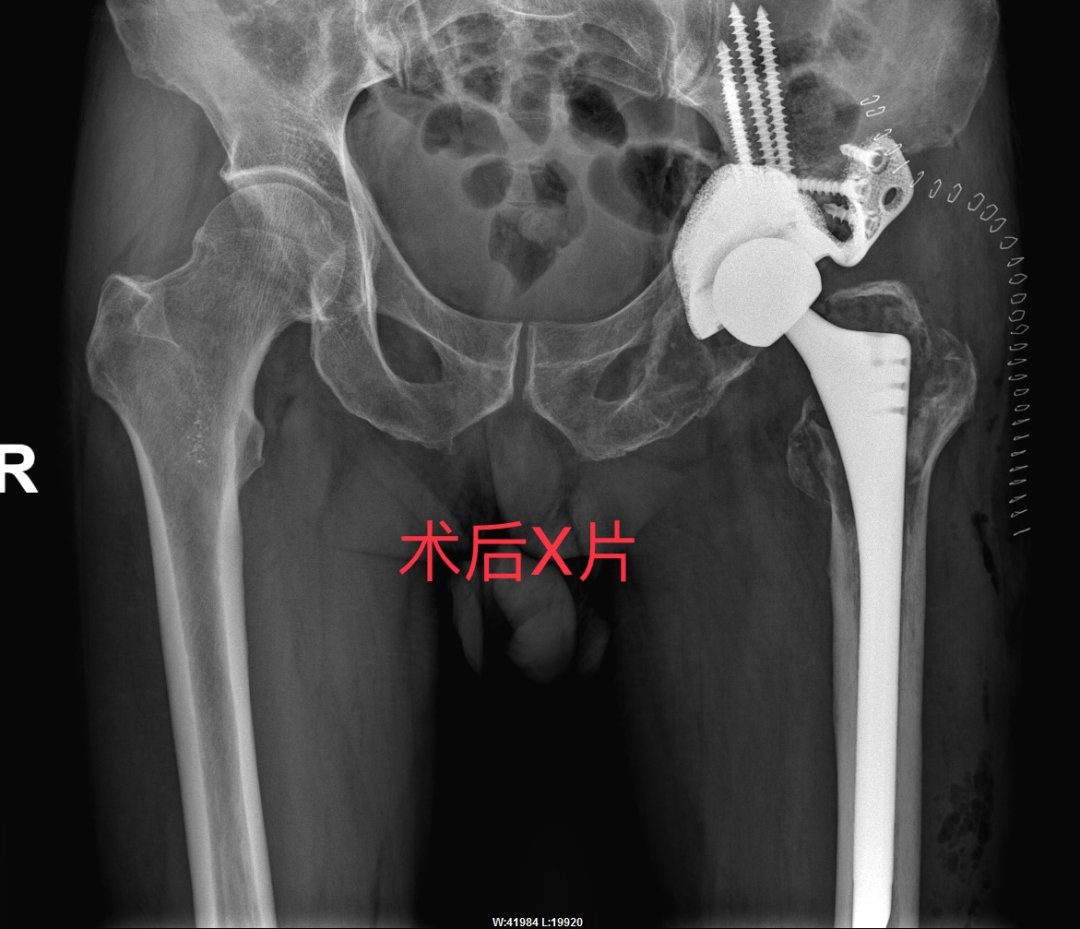

从卧床到康复仅24小时!

实现科技与医术的完美融合

曾爷爷的康复速度令人惊叹!

从卧床不起到行动自如

仅仅花了24 小时!

麻醉苏醒后,曾爷爷的髋关节已能无痛自由屈伸;术后24小时内,借助助行器就能行走,生活起居已能完全自理!

2. 3D打印与定制化假体

根据患者骨骼形态打印假体,解决复杂骨缺损(如Paprosky IIIB型),实现“严丝合缝”的固定。

3. 生物材料升级

使用钛合金+羟基磷灰石涂层假体,促进骨长入,降低松动风险;抗菌涂层技术减少感染概率。

4. 微创与导航技术

3D打印导板辅助精准植入,缩短手术时间,减少出血和神经损伤风险。